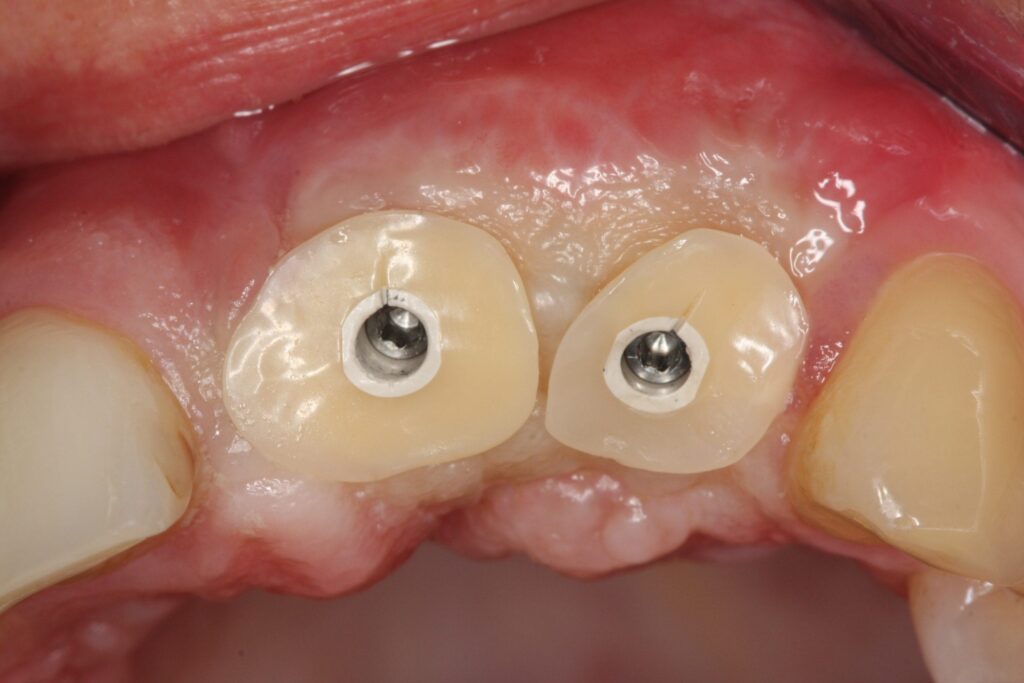

Implantat getragener Zahnersatz auf aufgebautem Eigenknochen

Nachdem die gewünschte Stabilität des Kieferknochens erreicht wurde, konnte Prof. Dr. Olze mit dem Setzen der Implantate beginnen. Um langfristig für Stabilität und Ästhetik zu sorgen und um einen erneuten Eingriff vermeiden zu können, wählte er in Absprache mit der Patientin hochwertige ANKYLOS®- Implantate und Zahnersatzkomponenten von Dentsply Sirona. Diese Versorgungslösung ermöglicht eine lange Haltbarkeit und mechanische Stabilität. Auch auf ästhetischer Ebene überzeugt diese qualitativ hochwertige Lösung. Hiermit ist sichergestellt, dass die Patientin auch nach Jahrzehnten noch unbeschwert lachen und abbeißen kann. Durch die innovative Knochenaufbaumethode und die nachhaltig konzipierten Implantatkomponenten wird einem späteren Knochenabbau entgegengewirkt und das Gewebe bleibt anhaltend stabil und gesund.